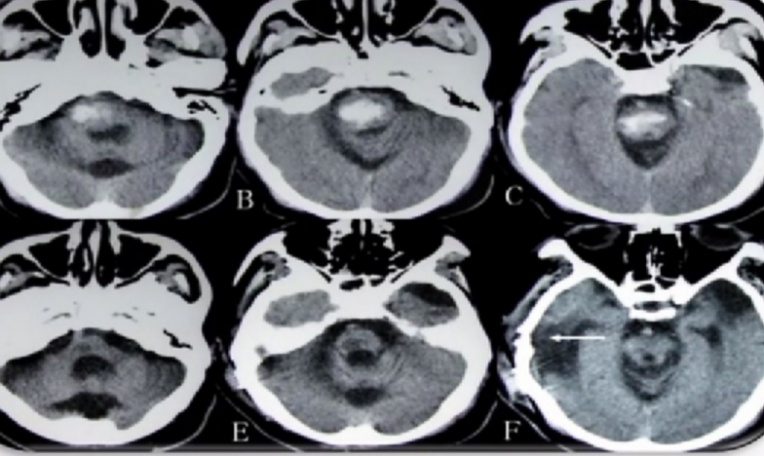

目前国内手术仍处于探索阶段,虽然临床观察疗效好,但缺乏RCT研究及有效、有力的证据。脑出血传统开颅血肿清除术虽然能够迅速清除血肿、去骨瓣减压以抢救生命。但是对正常脑组织牵拉重,创伤大, 水肿反应重, 术后不利于神经功能恢复, 死亡率高达28%~ 48%。所以不建议基层医院开展脑干出血的探索。而立体定向技术的问世,正好解决了临床工作中遇到的上述棘手问题。

自上世纪七十年代以后,立体定向技术在颅脑外科得到进一步的发展。特别是在CT、MRI等现代医学影像设备逐渐普及以后,微创立体定向手术在国内广泛开展,事实证明这一技术安全而且有效。该技术在挽救患者生命的同时能够较大程度减轻手术创伤。传统的脑立体定向手术必须借助于头部框架,方能定位和穿刺。立体定向框架一方面保证了定位的稳定性和准确性,但另一方面也限制了手术的方便性和灵活性。而“无框架脑立体定向技术”也被喻为“神经外科手术机器人”,避免了手术死角及患者安装常规框架的痛苦及恐惧心理,可在局麻下手术,创伤小,患者术后恢复快。